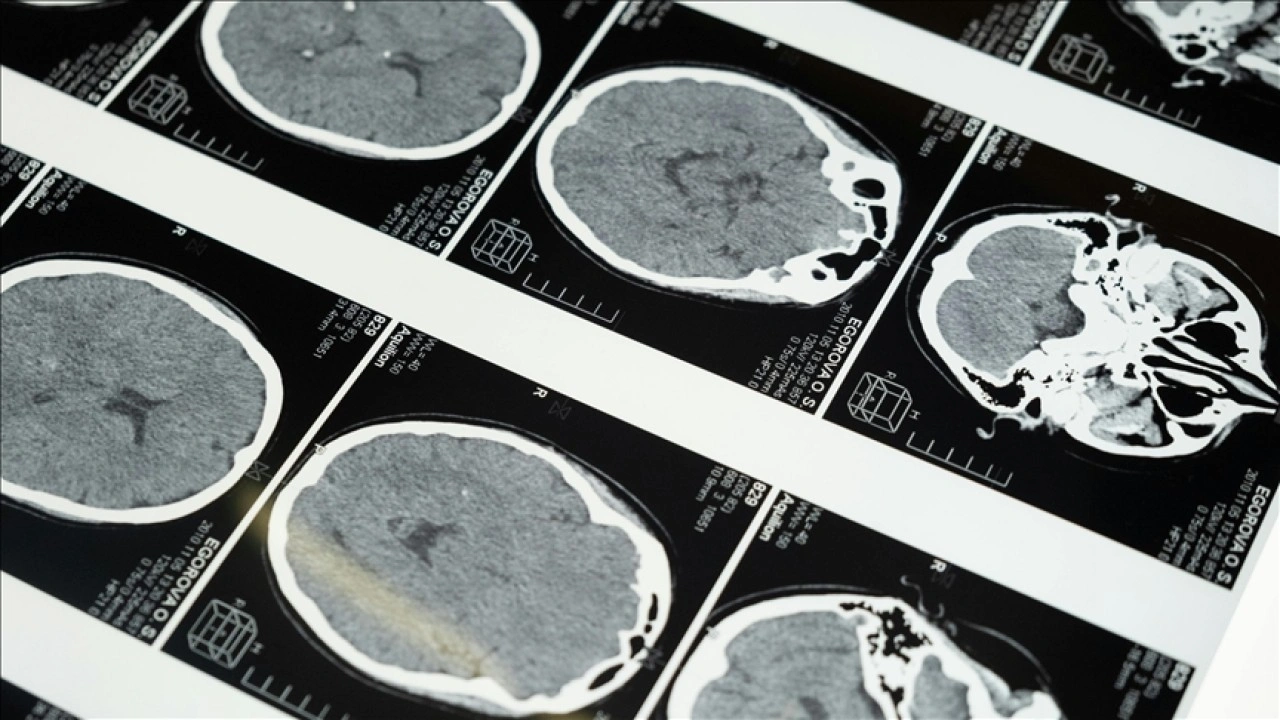

Uzun süre öz denetim gerektiren aktivitelerde bulunmanın etkilerini inceleyen bilim insanları, beyindeki elektriksel hareketlerin ölçümü için elektroensefalografi (EEG) başlığı taktığı 44 katılımcıyı 45 dakika boyunca duygusal videolar izlemek gibi bilgisayar temelli bazı uygulamalara tabi tuttu.